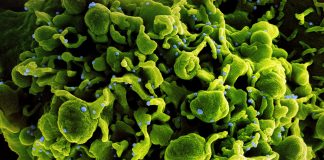

COVID-19 è una malattia infettiva respiratoria causata dal virus denominato SARS-CoV-2 appartenente alla famiglia dei coronavirus. Una malattia infettiva causata da un nuovo virus mai identificato prima negli esseri umani.